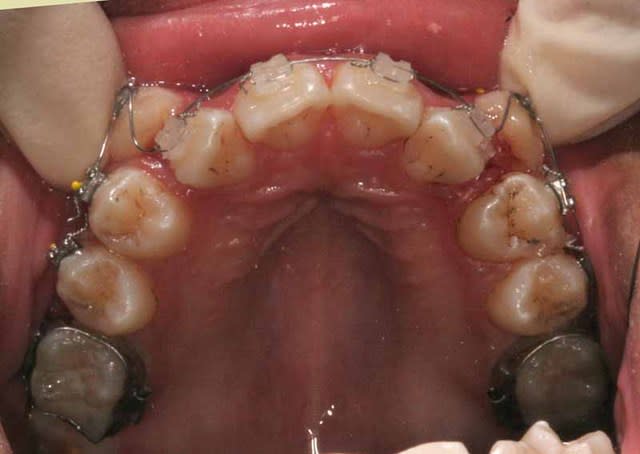

Vous vous rappelez de ce cas Damon ?

Image 1 qf9ljh - Eugenol